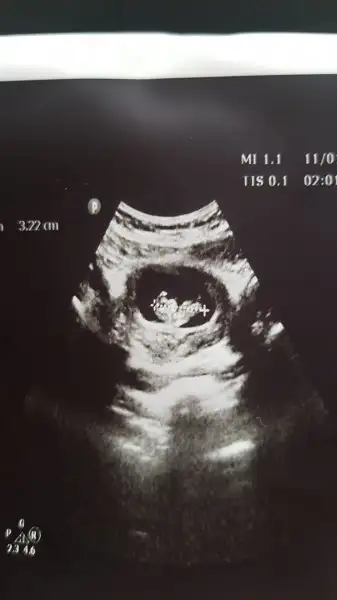

bebegin7-8 haftalıkkenki usg resimine direkt baktıgınızda;

bebek kesenin soluna yakınsa bebek erkek,

sagına yakınsa kız.

Mrb bende 9haftalık hamilymBu yöntem bircok kişide dogru sonuc verdii.

Biri 7 hafta 1 günlük biri 11 haftalık şuan 13 haftalık oldum acaba cinsiyeti ne olabilir tahmin de bulunabilir misiniz acaba Haftaya da doktora gidip net bi şekilde öğrenicem inşallah[/QU